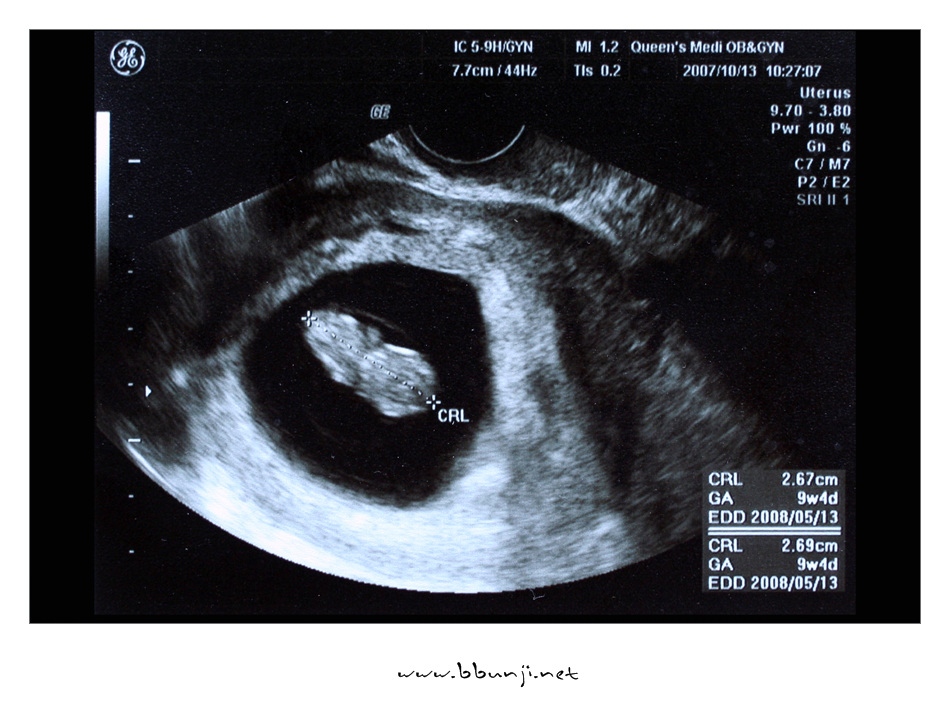

우리 사랑이~~~ 9주 4일째. *^^*

2007년 10월 13일

우와~ 키가 2.67cm 예전엔 그냥 점같이 콩알만했는데.. ^^

머리, 몸체, 다리 구분이 가능하네요.

심장소리 듣고 왔는데 쿵쾅쿵쾅 빨리 뛰는게 너무 희안해요.